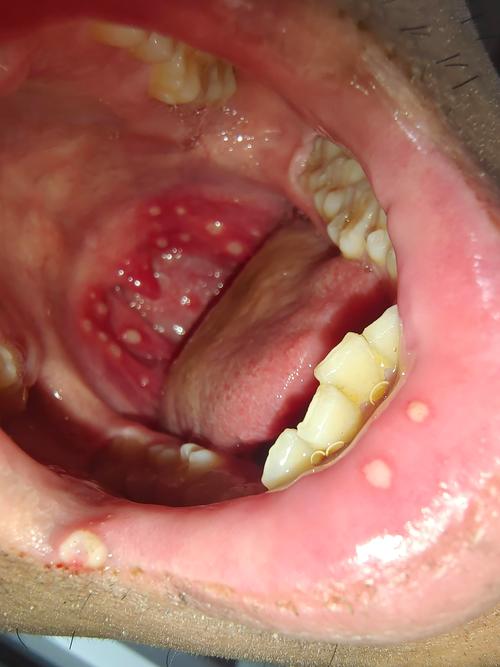

口腔溃疡白色上有红点是恶化信号吗?

这是什么?—— 溃疡的形成过程

您看到的这个现象,其实是口腔溃疡发展的一个正常阶段:

- 初期(红点/小红疱): 溃疡刚开始形成时,黏膜下的毛细血管会扩张、充血,形成一个边界清晰、微微凹陷的红色小点或小疱,这个阶段可能感觉不到疼痛,或者只是有轻微的异物感。

- 发展期(白色假膜): 这个红点中心的黏膜上皮会坏死、脱落,形成一个浅表的小凹陷,为了保护这个创面,炎症渗出的纤维素、坏死细胞和细菌会混合在一起,形成一层淡黄色或白色的薄膜,这就是您看到的“白色”部分,医学上称为“假膜” (Pseudomembrane),这层假膜本身没有痛觉神经,但它覆盖在下面暴露的神经末梢上,所以当您进食、说话或刷牙碰到它时,会引起明显的疼痛。

- 愈合期: 溃疡会逐渐缩小,白色假膜脱落,周围的红色炎症区域也会慢慢消退,最后恢复正常黏膜颜色。

“白色上有红点”是口腔溃疡正在处于活跃、疼痛阶段的典型标志。

您描述的“口腔溃疡白色上有红点”是口腔溃疡的典型表现,白色的假膜覆盖在发炎的红色黏膜上,因此会感到疼痛,这通常是良性的、自限性的,您可以通过调整生活习惯、使用局部药物来缓解症状、促进愈合。